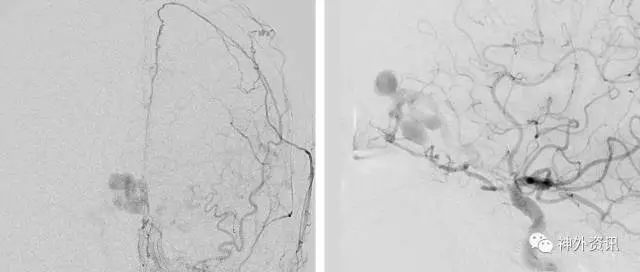

图1. 左侧颈外动脉的前后位血管造影(左图)和侧位血管造影(右图)提示筛骨dAVF,由筛前动脉和大脑镰动脉供血,引流至伴有静脉曲张的皮层静脉,可见静脉动脉化。

筛骨dAVFs位于前颅窝底,由筛前动脉、眼动脉脑膜支和起源自眼动脉的大脑镰前动脉供血,形成瘘口样连接,在额叶下方前颅窝硬脑膜基底部或内侧的大脑镰引流至一根软脑膜静脉(额静脉或嗅静脉)。